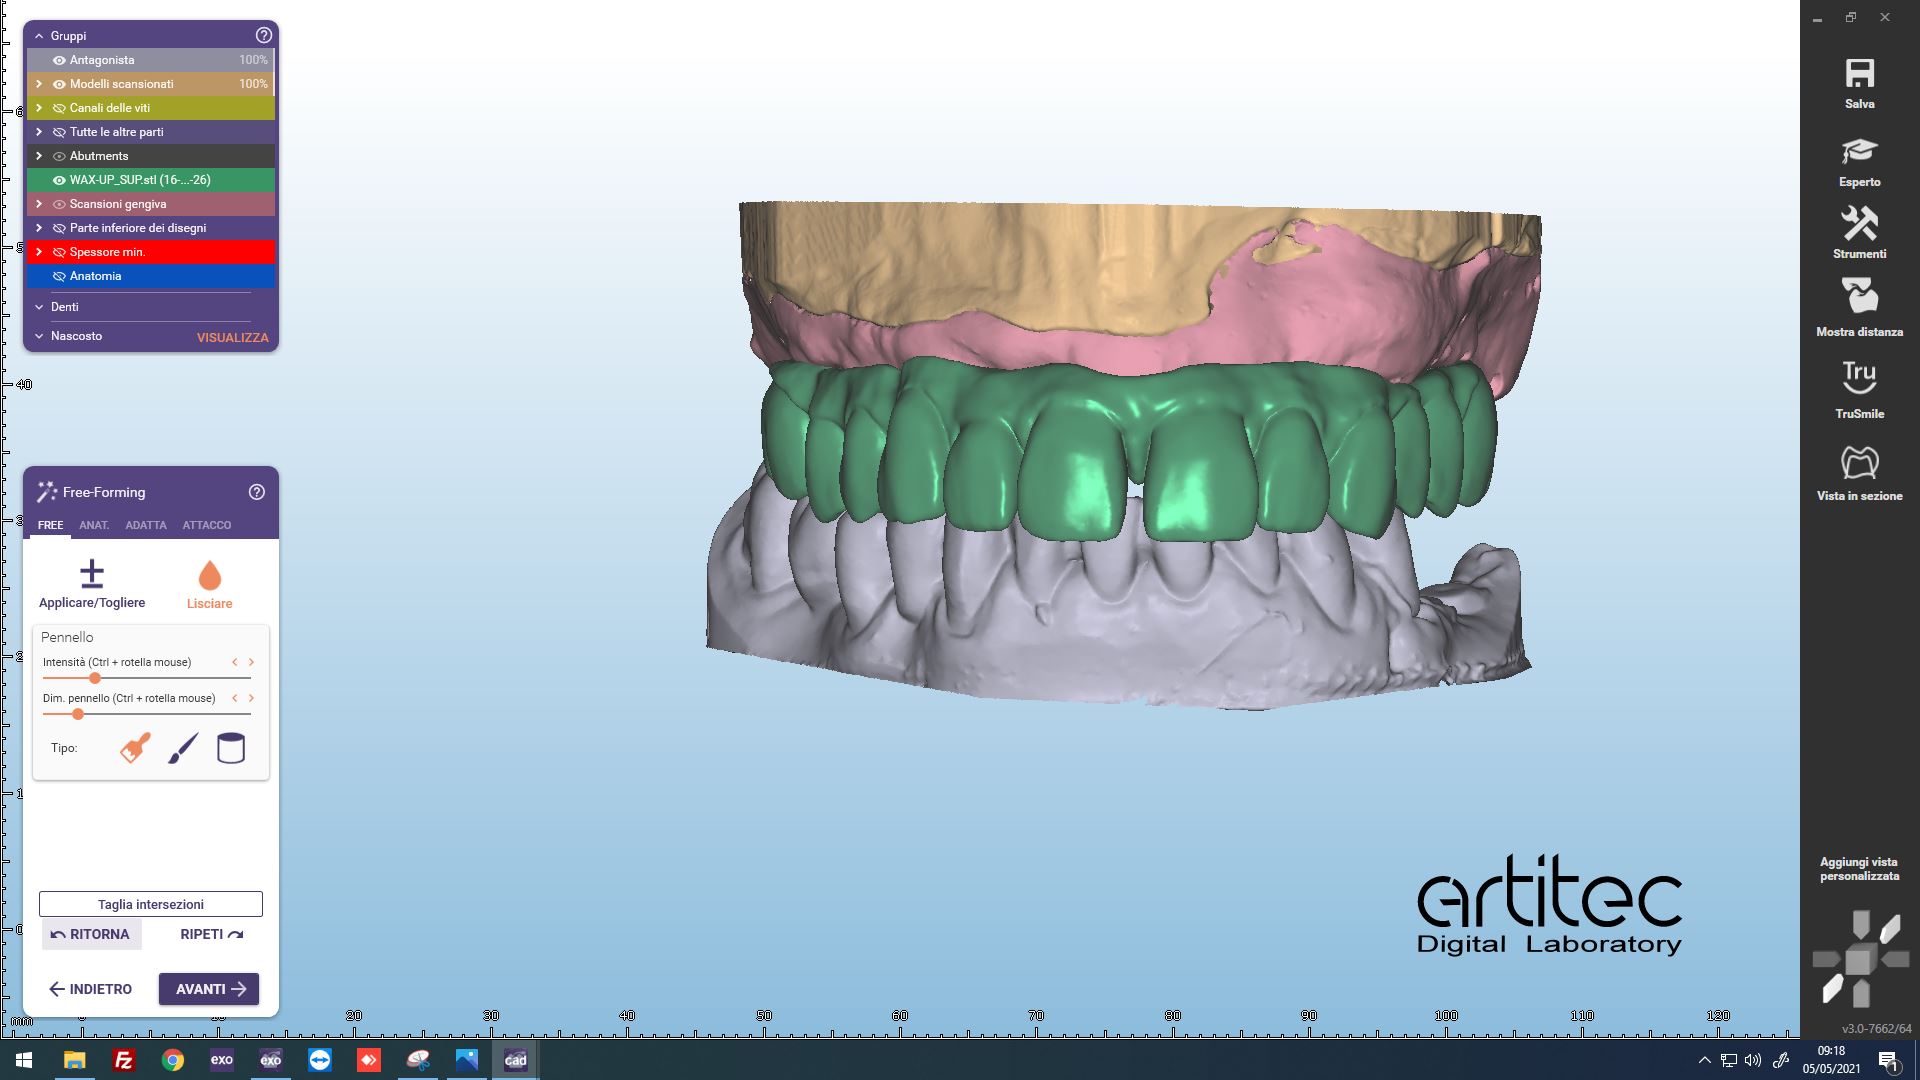

Fig. 9 Anatomie del progetto virtuale del defintivo